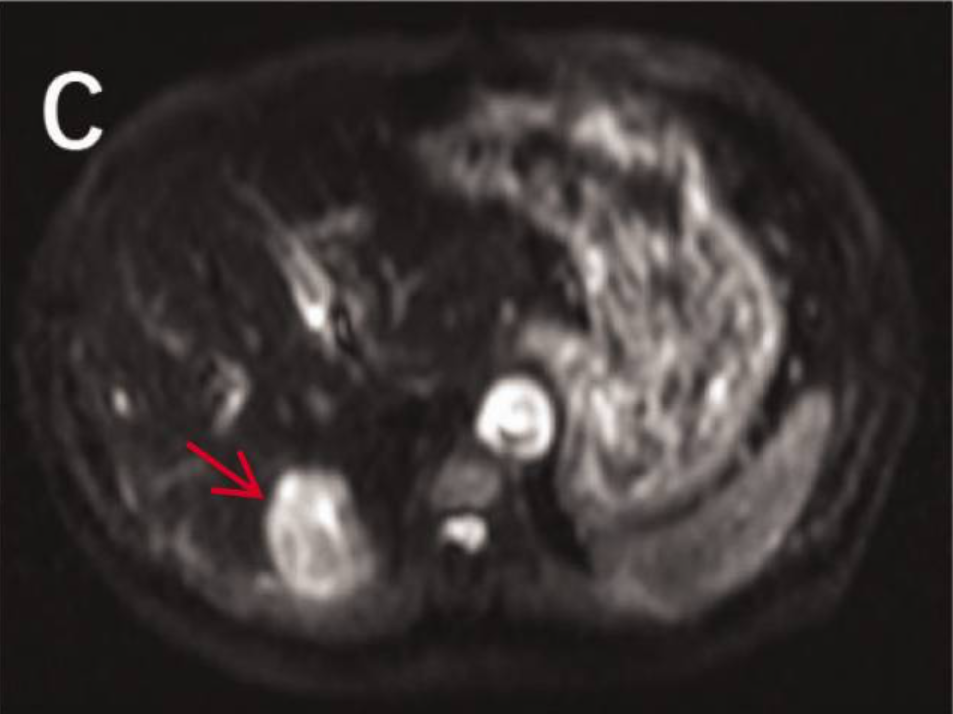

病史摘要:30岁男性患者,有大量饮酒史,无吸烟及非法药物使用史,否认胃肠道恶性肿瘤等家族史。因精神状态改变被送至急诊科。 诊疗过程:初始检查发现中度转氨酶升高,尿毒物筛查大麻素阳性,多种病毒血清学阴性。影像学检查发现孤立性左肾、输尿管结石伴急性肾损伤及腹腔肿块等。肿瘤标志物大多正常,LDH升高等。CT引导下活检,病理及免疫组化有相应表现。初步诊断为起源于胰腺的异位肝细胞癌伴广泛转移,先接受